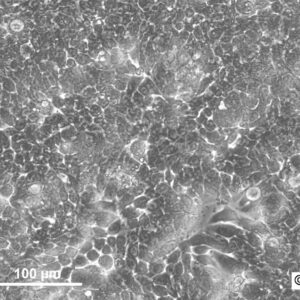

Morphology: Epithelial-like

Growth Properties: Adherent

Description: HuH7 was established in 1982 by Nakabayashi et al. from a 57-year-old Japanese male with well differentiated hepatocellular carcinoma.